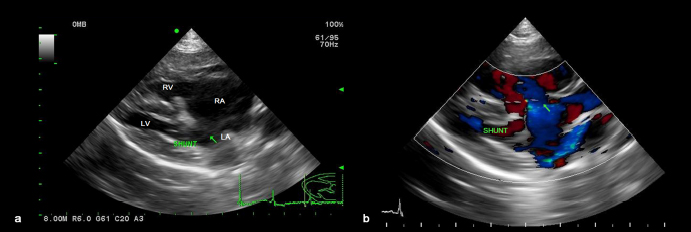

A 1-year-old neutered male Maltese dog weighing 1.4 kg was referred to the Veterinary Teaching Hospital showing microhepatica (Fig. 1a) and hyperammonemia. The dog did not show clinical signs related to portosystemic shunt previously. Although its postprandial ammonia level was in the reference range [18 μmol/l, reference interval (RI): 0–98 μmol/l], hypoalbuminemia (2.1 g/dl, RI: 2.6–3.3 g/dl) and increased levels of serum bile acid (177 μmol/l, RI: 0–25 μmol/l), alanine transaminase (ALT) (254 IU/l, RI: 21–102 IU/l), and alkaline phosphatase (ALP) (1347 IU/l, RI: 29–97 IU/l) were identified. No abnormalities, including cardiac murmur, were observed during physical examination. For a more thorough examination, computed tomography was used, and a CPSS (porto-caval shunt) was diagnosed (Fig. 2a and b). After preoperative medical stabilization, surgery was performed for shunt attenuation. Anesthesia was induced with propofol (8 mg/kg, IV) and maintained by isoflurane. Perioperative pain was managed by tramadol (5 mg/kg, IV). From the xiphoid process to the pubis, a standard ventral midline approach was taken. After dissecting the shunt from surrounding tissues, portal pressure was measured from the jejunal vein. Baseline portal pressure was measured to be approximately 7–8 mmHg (RI: 6–10 mmHg). It increased to 13–14 mmHg after temporary complete occlusion of the shunt. The shunt was attenuated using a cellophane band. The abdominal cavity was closed in a routine manner. Its recovery from anesthesia was uneventful. Postprandial serum bile acid (12 μmol/l), albumin (2.6 g/dl), and ALT (29 IU/l) levels returned to their normal ranges at 1 month after the operation. Its serum ALP level also decreased to 430 IU/l, although it was above the RI. An increase in liver size was observed by abdominal radiographs 1 month after surgery (Fig. 1b). Because the majority of the CPSS anomalies were cured throughout the follow-up period, the dog was able to return to normal life without the need for supporting medicine. One year after surgery, the dog was presented to the Veterinary Teaching Hospital for exercise intolerance. Blood gas analysis revealed hypoxemia (73.6%, RI: 95%–99%). A cardiac murmur was auscultated. When compared with thoracic radiographs evaluated at the time of the operation (Fig. 3a and b), the vertebral heart scale increased from 10 to 11.7, indicating generalized cardiomegaly (Fig. 3c and d). Following echocardiography revealed ASD and pulmonary hypertension (Fig. 4a and b). A bubble study confirmed right-to-left shunt. Surgical or interventional therapy was not contemplated due to the dog's tiny size (1.7 kg) and reversed interatrial shunt. Thus, medical treatment was performed to reduce pulmonary hypertension (sildenafil, 1.5 mg/kg, PO, q12 hours). Hypoxemia was improved (94%) after a month of treatment. The dog's activity intolerance had been overcome, according to the owner. As a response to the medical treatment was generally good, therapy was still maintained without changing medication for the next 16 months after diagnosis of the ASD.

Fig. 3. Thoracic radiographs. When compared with preoperative images (a, b), generalized cardiomegaly was observed at one year after the operation (c, d).

The present study described a dog with two types of vascular anomalies. Similar to a previous study (Greenhalgh et al., 2010), the dog showed a good prognosis after surgical attenuation of the CPSS. Cardiomegaly was not seen on preoperative thoracic radiographs, despite the fact that ASD was suspected at the time of CPSS diagnosis. ASD is generally a well-compensated disease (Chetboul et al., 2006) and the dog may show no clinical symptoms over 2 years. When it was presented 1 year after the operation, the chief complaint was exercise intolerance of the dog. Compared with the previous clinical data on the dog, it could be suspected that ASD caused pulmonary hypertension, which might have resulted in a right-to-left shunt (Guglielmini et al., 2002). This hemodynamic physiology is generally defined as Eisenmenger’s syndrome, which can cause cyanosis and exercise intolerance (Berger et al., 2010). In veterinary medicine, surgical treatment for ASD is challenging for small-sized dogs (Pelosi et al., 2013). Although a case of ASD closure in a toy poodle was recently published (Sugimoto et al., 2020), owing to the dog's pulmonary hypertension and reversed interatrial shunt, surgical and interventional therapy for the dog was not explored in the current investigation. Surgical treatment for Eisenmenger’s syndrome, such as heart-lung transplantation, has been performed in human medicine. However, its morbidity and mortality remain high (Waddell et al., 2002). As an alternative to surgical treatment, medical management by sildenafil can be effectively applied to patients with this condition (Garg et al., 2011). The dog in the present study also responded well to sildenafil, and its clinical symptoms were resolved. In previous human medicine studies, about 9% to 30% of patients have CPSS concurrent with ASD (Franchi-Abella et al., 2010; Kim et al., 2012). Like human medicine, this study reports a rare case of CPSS concurrent with ASD in a dog. Because congenital heart illnesses are easily recognized by echocardiography, it is also suggested for dogs with CPSS to get an echocardiogram for early detection of additional cardiovascular defects, even if there are no symptoms.